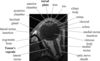

FIGURE 31-5 Basal encephalocele.A, A sagittal T1-weighted image shows callosal agenesis with a tiny lipoma (arrow). A large defect in the basisphenoid is seen. Note the apparent absence of the pituitary, floor of the third ventricle, and optic pathways. B, A high-resolution sagittal T2-weighted image shows the pituitary-hypothalamic structures (arrow) and optic pathways are contained within the encephalocele.